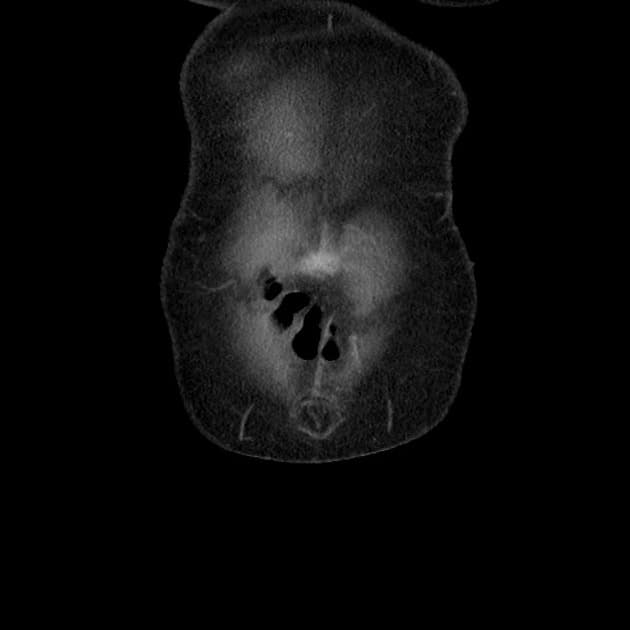

MRCP

Có hiện tượng tắc nghẽn ống tụy chính tại mức cổ tụy, kèm giãn nhẹ ống chính phía trên (2 mm). Một vùng tròn giới hạn không rõ kích thước khoảng 2 cm ở đầu tụy có tín hiệu T2 tăng nhẹ, nằm gần vị trí tắc ống tụy chính. Tín hiệu hình ảnh khuếch tán (DWI) tăng nhẹ lan tỏa và thể tích tụy tăng nhẹ. Không có dịch quanh tụy hay viêm khu trú.